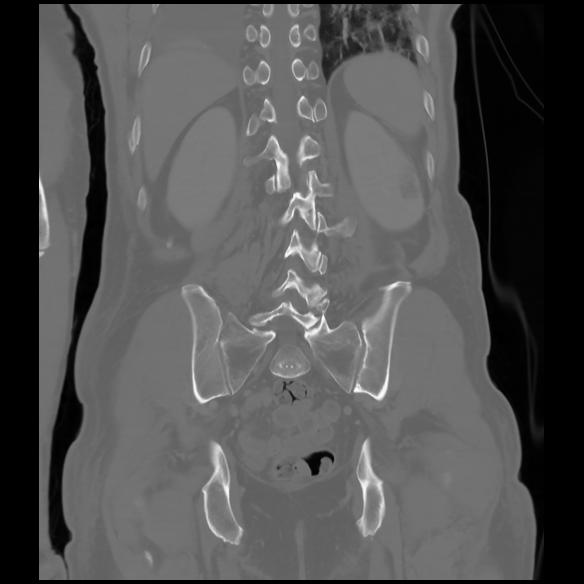

6 CUERPO,CE,Coronal,3.000,CUERPO,Coronal,